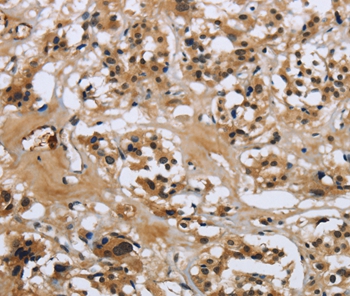

Immunohistochemical analysis of paraffin-embedded Human thyroid cancer tissue using #36880 at dilution 1/50.

Immunohistochemical analysis of paraffin-embedded Human tonsil tissue using #36880 at dilution 1/50.